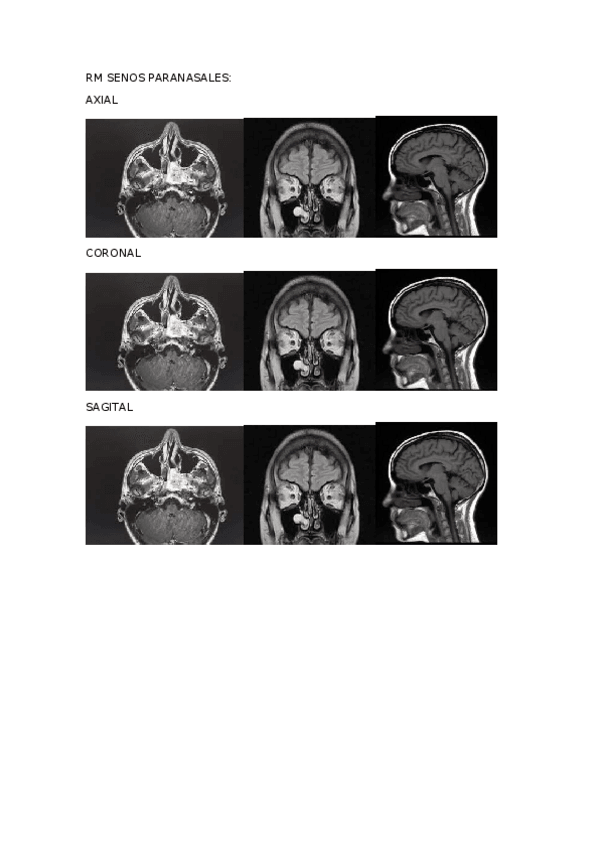

He publicado nuevos apuntes de Técnicas de Imagen por Resonancia Magnética: ACTIVIDADES-RM-1.docx

word